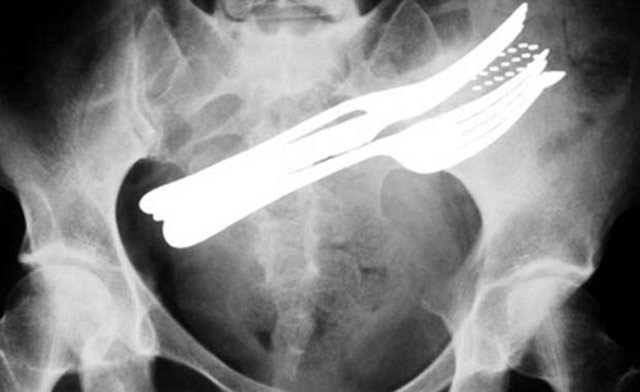

Röntgen filmlerinden "akıl almaz şeyler

Hastane koridorlarına düşenler bilir… Doktora görün, tahlilleri yaptır, röntgenleri çektir falan filan derken sayılmadan ömür gider. Gelin ki bu sefer ilginç şeyler çıkmış ki görün ağzımız açık kaldı…